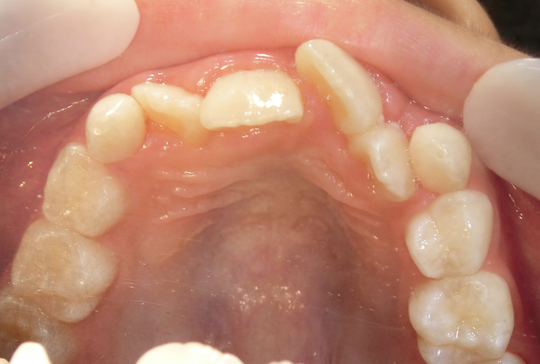

治療前

治療説明

歯科矯正で取り外し可能な矯正方法である床矯正とチンキャップで治療しました

治療期間 4年6か月

治療費用300000 円

治療後

治療の副作用(リスク)歯の動き方には個人差があり、予想された治療期間が延長する可能性があります。。床矯正の使用状況、矯正歯科治療には患者さんの協力が必要であり、それらが治療結果や治療期間に影響します。2次矯正が必要になる場合もあります。